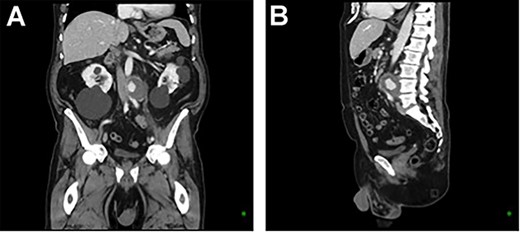

A 73-year-old male presented with a 1-week history of back pain on a background of hypertension, atrial fibrillation and bladder cancer. Computed tomography (CT) angiography demonstrated a 47 × 46 × 47 mm saccular aortic pseudoaneurysm of the infrarenal aorta with a contained rupture (Fig. 1). The patient remained hemodynamically stable with mildly elevated inflammatory markers (C-Reactive Protein (CRP), 85 mg/l, white cell count (WCC) 6.5 × 109/l). The abdominal aorta 5 months previously was normal on CT when a course of intra-vesical BCG for transitional cell carcinoma of the bladder had been ceased due to the development of fevers and syncope. Thus, Mycobacterium bovis involvement of the false aneurysm was suspected. Emergent endovascular repair was performed with a covered stent graft system successfully excluding the ruptured aneurysm sac on post-operative CT angiogram. A CT-guided fine needle aspirate of the aneurysmal sac was later conducted (Fig. 2). PCR of the aspirate returned a low-positive result confirming the diagnosis with M. bovis subsequently isolated on culture. Empirical antibiotics were ceased and he was commenced on a planned 18-month antituberculosis regimen of ethambutol, isoniazid and rifampicin guided by gene deletion analysis (GeneXpert MTB/RIF Ultra assay). Fluorodeoxyglucose-positron emission tomography (FDG-PET) scan was used to monitor the level of activity of the infection (Fig. 3). The patient was discharged home on Day 10 of admission. Aneurysm sac size was decreased at 3 and 6 months on CT angiogram and FDG-PET but there was ongoing FDG avidity around the aneurysm sac; there were no other sites of involvement. The patient remains otherwise well and has returned to his premorbid activities.

CT angiography post endovascular repair demonstrates an aorto-bi-iliac stent graft extending from the infrarenal aorta to the common iliac arteries with a small area of persistent filling of the pseudoaneurysm that subsequently resolved.